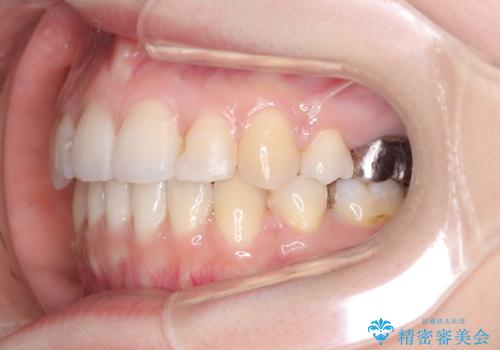

- 主訴:口元を下げて前突感を無くしたい、下の歯の凹凸も無くしたい

右側第二小臼歯、左側第一小臼歯、下顎両側第一大臼歯を抜歯しワイヤ-矯正を行いました。

骨格的顎の変位を認めたため、顔貌に対しピッタリ上下の歯の正中を合わせることは難しいと説明し、上下左右計4本小臼歯を抜歯しワイヤー矯正治療を行いました。